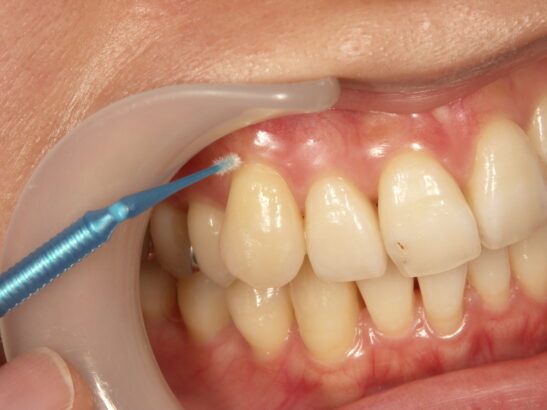

薬を塗る

象牙質に専用の知覚過敏抑制剤を塗ることで薬剤の成分(フッ化ナトリウム含有、シュウ酸カリウムベース・硝酸カリウム)と歯質のカルシウムが反応し、象牙細管内及び塗布表面に保護皮膜を形成して象牙細管を緊密に封鎖し、刺激が伝わりにくいようにします。